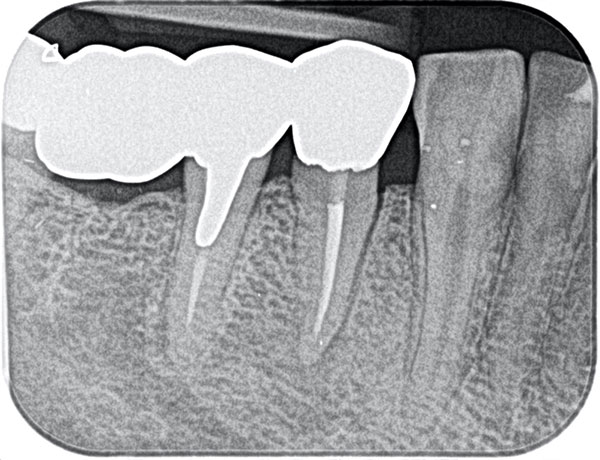

主訴: 噛むと痛い、左で食べれない。他の病院で神経が見つからない。根の先に病気がある。

通常だと手立てがなく、抜歯しかない歯も外科(根尖切除術)で治すことができます。

歯茎が腫れ、CT上では骨が大きくないことがわかります